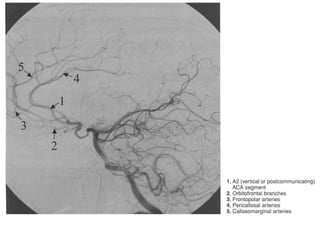

Segmentação da ACA

• A1 (pré-comunicante): . acima do quiasma óptico até unir-se

a AComA. A hipoplasia desse segmento correlacionasse

com a formação de aneurismas.

• A2 (infracaloso): começa na AcomA, dirige à lamina

terminal e termina na junção do rostro do corpo caloso.

• A3 (pré-caloso): se estende em torno do joelho e termina

onde a artéria se curva abruptamente para sentindo

porterior.

• A4 (supracoloso): porção anterior do segmento horizontal

• A5 (caloso posterior): porção posterior do segmento

horizontal